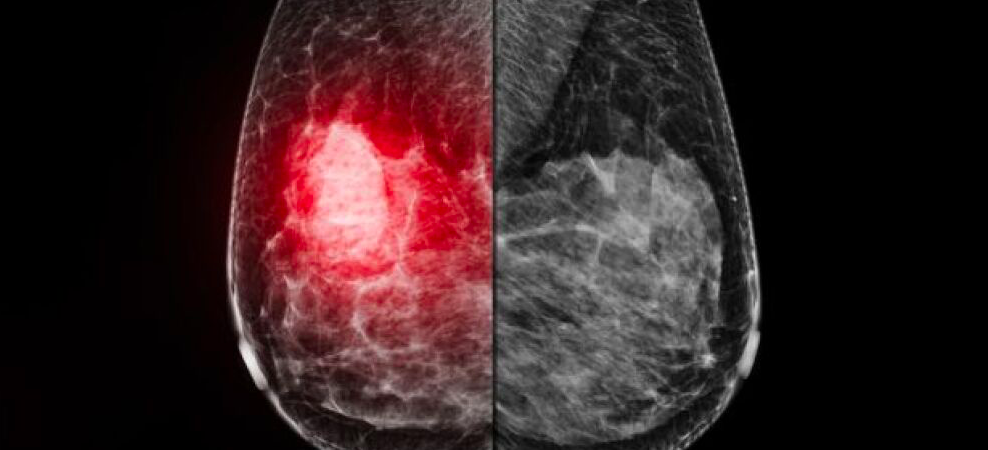

The MOLLI 2 System is an innovative technology that allows radiologists to mark lesions with the MOLLI Marker, a localization device roughly the size of a sesame seed. The device can be placed up to 30 days before surgery, allowing radiology to make the best use of time in the mammography suite without the need to synchronize schedules with surgery. Surgeons then use the MOLLI® Wand and MOLLI® Tablet to locate the lesion marked in radiology reliably, eliminating the need for wire-guided localization. The technology features a market-leading innovation — directional 3D guidance — which enables MOLLI 2 to direct surgeons to the lesion with millimeter precision. The MOLLI 2 System is easy to use, reliable, and precise, improving efficiency and enhancing the patient experience.